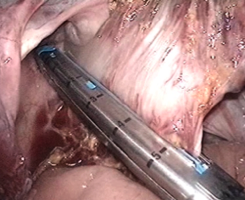

カッターとホッチキスが合体したような器械で、大腸を切り離します。

この後、お腹の一番下の傷を4cmに広げて腸を引き出し、大腸の口側をお腹の外で切り離します。

これで、病気の部分を含んだ大腸が切除されます。